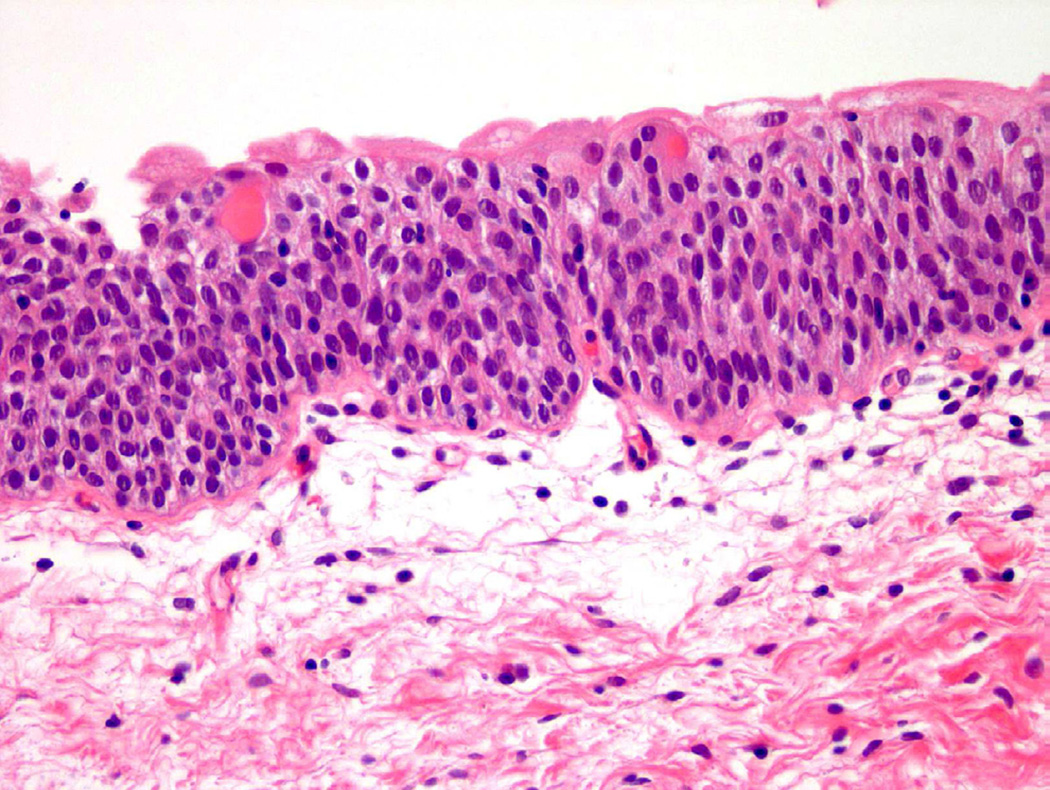

From a histologic perspective, “atypia” refers to a presence of one or more cellular or architectural features that deviate from that of an otherwise normal appearing cell or group of cells. Under normal conditions, urothelial cells contain oval nuclei, finely stippled chromatin, and minute to absent nucleoli, as well as ample cytoplasm and distinct cell membranes (Fig. 1)2. Even within the spectrum of “normal”, urothelial cells are permitted to have certain variations in cell size and cytoplasm, particularly in the most superficial layer of the urothelium (umbrella cell layer), which is in constant contact with the contents of the urinary space. These umbrella cells tend to be larger than cells in the intermediate and basal layers, with occasional binucleation and abundant eosinophilic cytoplasm. To further complicate matters for the pathologist, bladder distension can lead to flattening of superficial (or umbrella) cells to a point where the layer can be difficult to identify microscopically3.

Figure 1.

Normal urothelium.